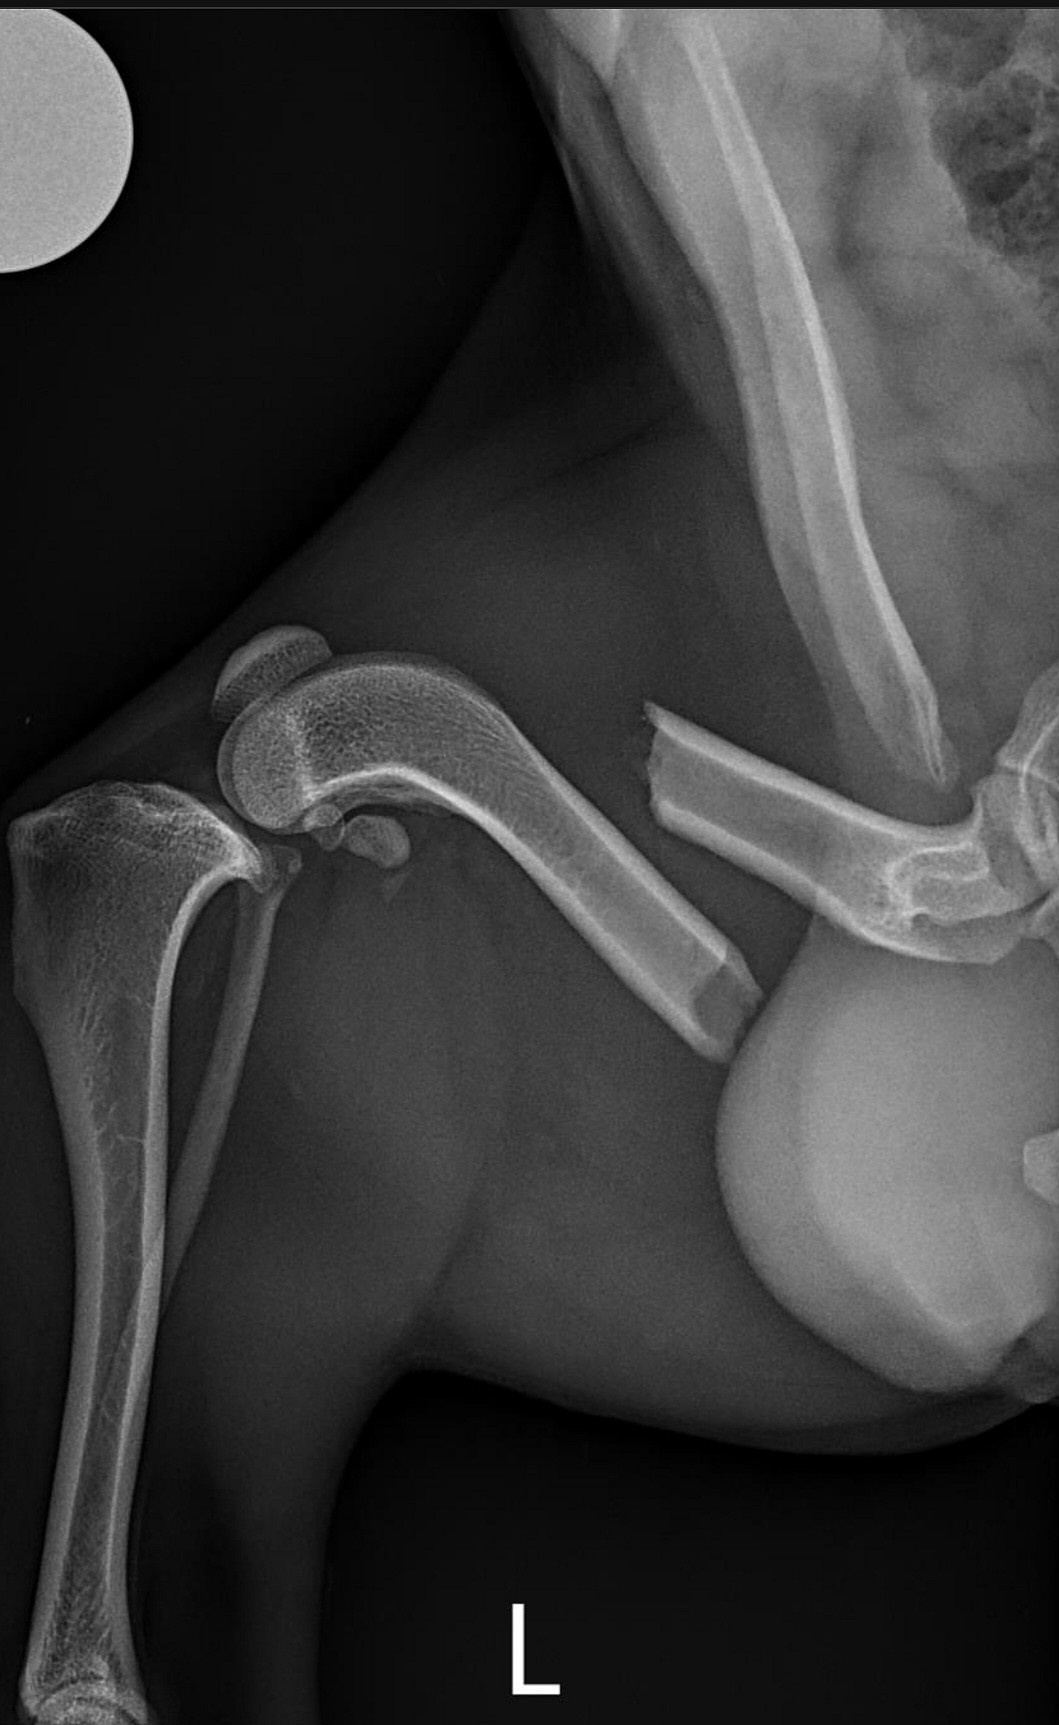

Mikey was taken to an orthopedic surgeon for examination. X-rays revealed a femur fracture on Mikey’s left back leg. The vet described it as a straight, clean break. However, due to the amount of scar tissue that had formed around the break, and because significant time had passed since the initial injury, Mikey would require surgery. The procedure was scheduled for Wednesday, March 27th.